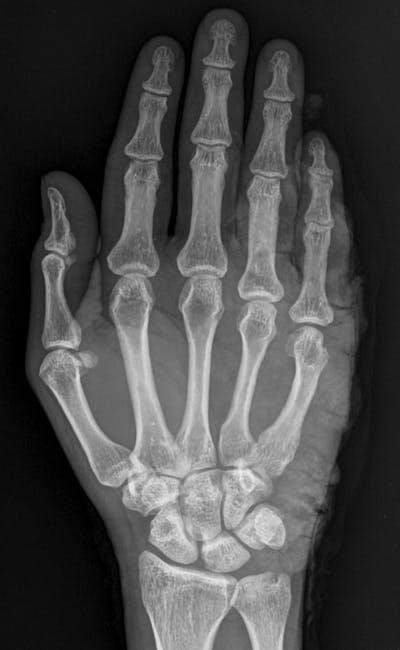

Bone Classification

Essential laboratory exercises focus on categorizing bones – long, short, flat, irregular, and sesamoid – based on shape and function․ Manuals aid in identifying these types through observation and dissection․ Understanding classification is crucial for grasping skeletal anatomy, as detailed in lab resources available since January 15, 2026, and is vital for comprehending biomechanics and movement․

Bone Markings

Essential lab work involves identifying bone markings – projections, depressions, and openings – serving as muscle attachment sites or passageways for vessels and nerves․ Manuals guide students in recognizing features like tubercles, foramina, and fossae․ Accurate identification, starting January 15, 2026, is key to understanding skeletal function and anatomical relationships․